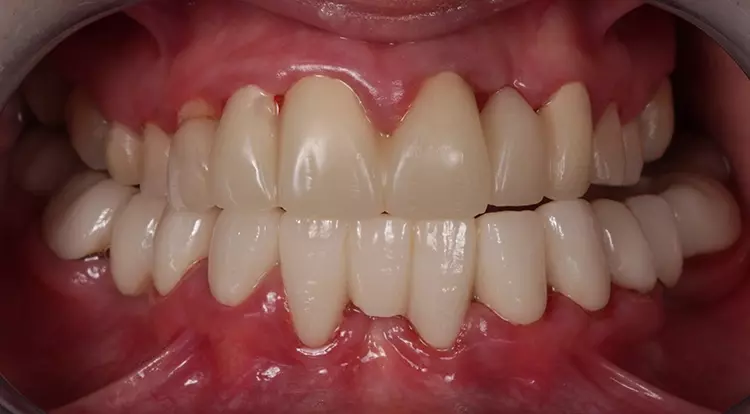

Eine 35-jährige Patientin stellte sich auf Empfehlung eines Kollegen mit einem sanierungsbedürftigen, parodontal (Parodontitis apicalis) geschädigten Gebiss vor. Zudem zeigten sich Verspannungen im Schulter- und Nackenbereich. Sie wies darauf hin, dass sich aufgrund einer angefangenen prothetischen Sanieriung in der jüngsten Vergangenheit das Kauvermögen deutlich reduziert hat und die Gebisssituation besonders in der oberen Front sich immer weiter verschlechtert hat. Laut eigener Aussage „würden die Zähne nicht mehr richtig aufeinanderpassen“ und seit der angefangenen Sanierung im UK „wäre das Kauen nur noch eingeschränkt möglich“ (Abb. 1 und 2).

Sie litt zudem an überempfindlichen Zahnhälsen im Bereich der Prämolaren und Molaren beidseits. Vor ungefähr 15 Jahren wurde laut Patientin die erste „Full-Mouth-Rekonstruktion“ in Mazedonien durchgeführt. Die klinische Funktionsanalyse zeigte positive parafunktionelle Befunde (okklusaler Index 1,4 „kompensiert +“), die bei der Patientin regelmäßig zu Kopfschmerzen sowie starken Beschwerden beim Kauen und Schlucken führten.